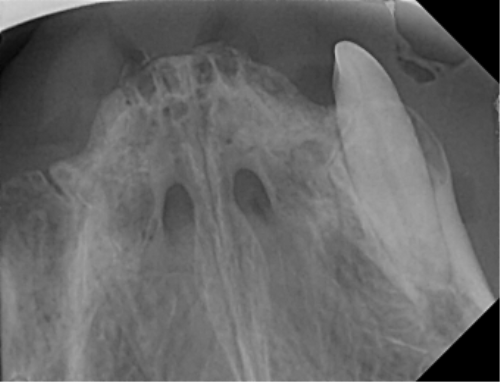

| 치료과정 | -다행히 상추는 금세 포획이 되어서 2번 시도 만에 병원으로 데려갈 수 있었습니다. -많이 마르고 구내염이 꽤 지속된 상태로 보여 검사 후 수술을 진행하기로 했습니다. 방사선, 초음파, 혈액검사를 진행했고 검사상 감사하게도 수술이 가능한 수치가 나왔습니다. 더 못 먹고 염증이 지속될 경우 건강이 더 상할 것 같아 바로 수술을 진행하였습니다. -진통 패치 및 진통제, 항생제 처방을 해주시고 먹는 것을 병원에서 관찰해주셔서 소식을 전해 들을 수 있었습니다. 아이는 첫날 조금밖에 먹지 않았으나 다음날부터 습식에 비벼 준 사료 등을 두 그릇씩 먹으며 씩씩하게 지내주었습니다. 병원 케어를 좀 더 받았으면 하여 일주일 정도 입원을 하였고 피하수액 등을 하여 탈수도 교정이 좀 되었으면 하는 심정이었습니다. -병원에서 마취 상태에서 입 안 사진을 찍어 기록한 후 보여주셨는데 꽤 심각했습니다. 목구멍 쪽 증식한 염증을 많이 절제하였고 레이저 치료까지 진행하였습니다. 치아 엑스레이 촬영도 모두 보내주셔서 기록해두는 데 도움이 되었습니다. -아이가 자발 식이를 잘 할 경우 퇴원을 해도 되기에 집에서 회복 공간을 만들어주었습니다. 나가고 싶은 듯 바깥을 보며 처음에 힘들어했지만 점차 적응하며 편안하게 휴식을 했습니다. 밥은 꼬박꼬박 두 그릇 넘게 챙겨 먹었고 소화가 잘 되는 습식 위주로 주었습니다. 건사료를 언제쯤 먹을 수 있나 관찰하려 두었더니 며칠 안에 금세 먹었습니다. 알갱이 작은 사료를 주었으나 기존에 먹던 맛을 먹고 싶은지 그것만 먹었습니다. |

| 대상묘 치료중 사진 |          |